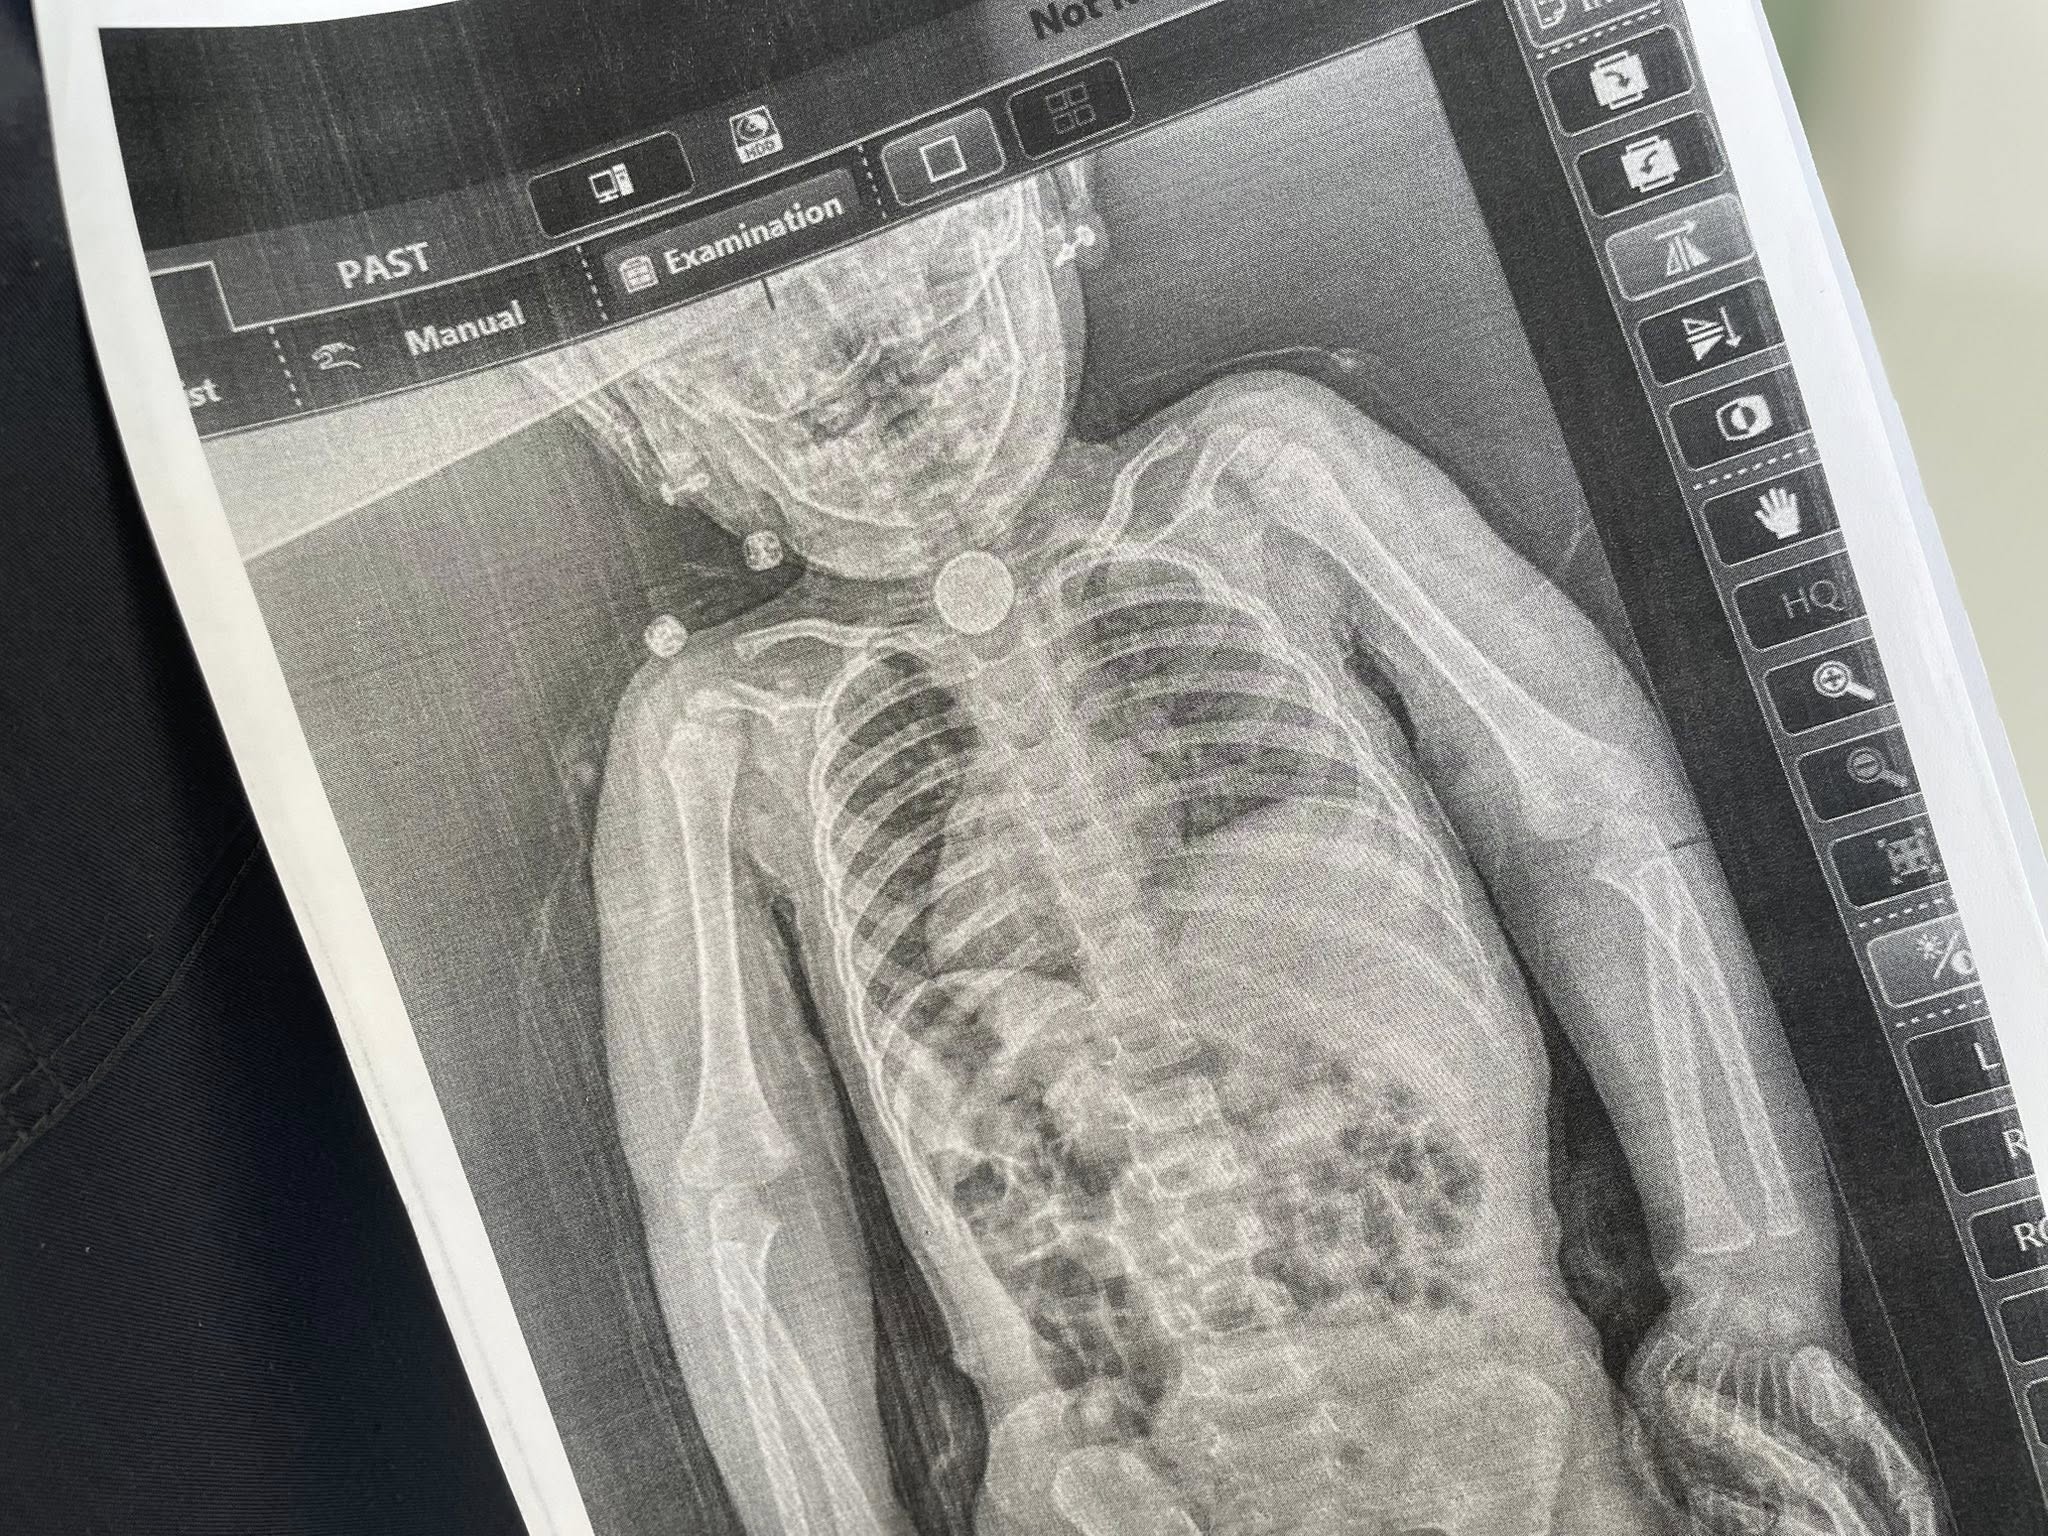

Проте, як зауважують у лікарні, на початку весни у дитини з’явилися нові небезпечні симптоми: блювання, відмова від їжі, покашлювання та свистяче дихання, яке було чути навіть на відстані. Відтак, батьки знову звернулися до спеціалістів. Дівчинці зробили рентген, який чітко показав стороннє тіло у стравоході.

Як з'ясувалося, у стравоході дитини міцно застрягла кругла літієва батарейка діаметром 2,5 сантиметра, а навколо неї сформувалися набряк. Операція була вкрай складною, адже існував ризик розриву стравоходу. Проте оперативне втручання пройшло успішно.